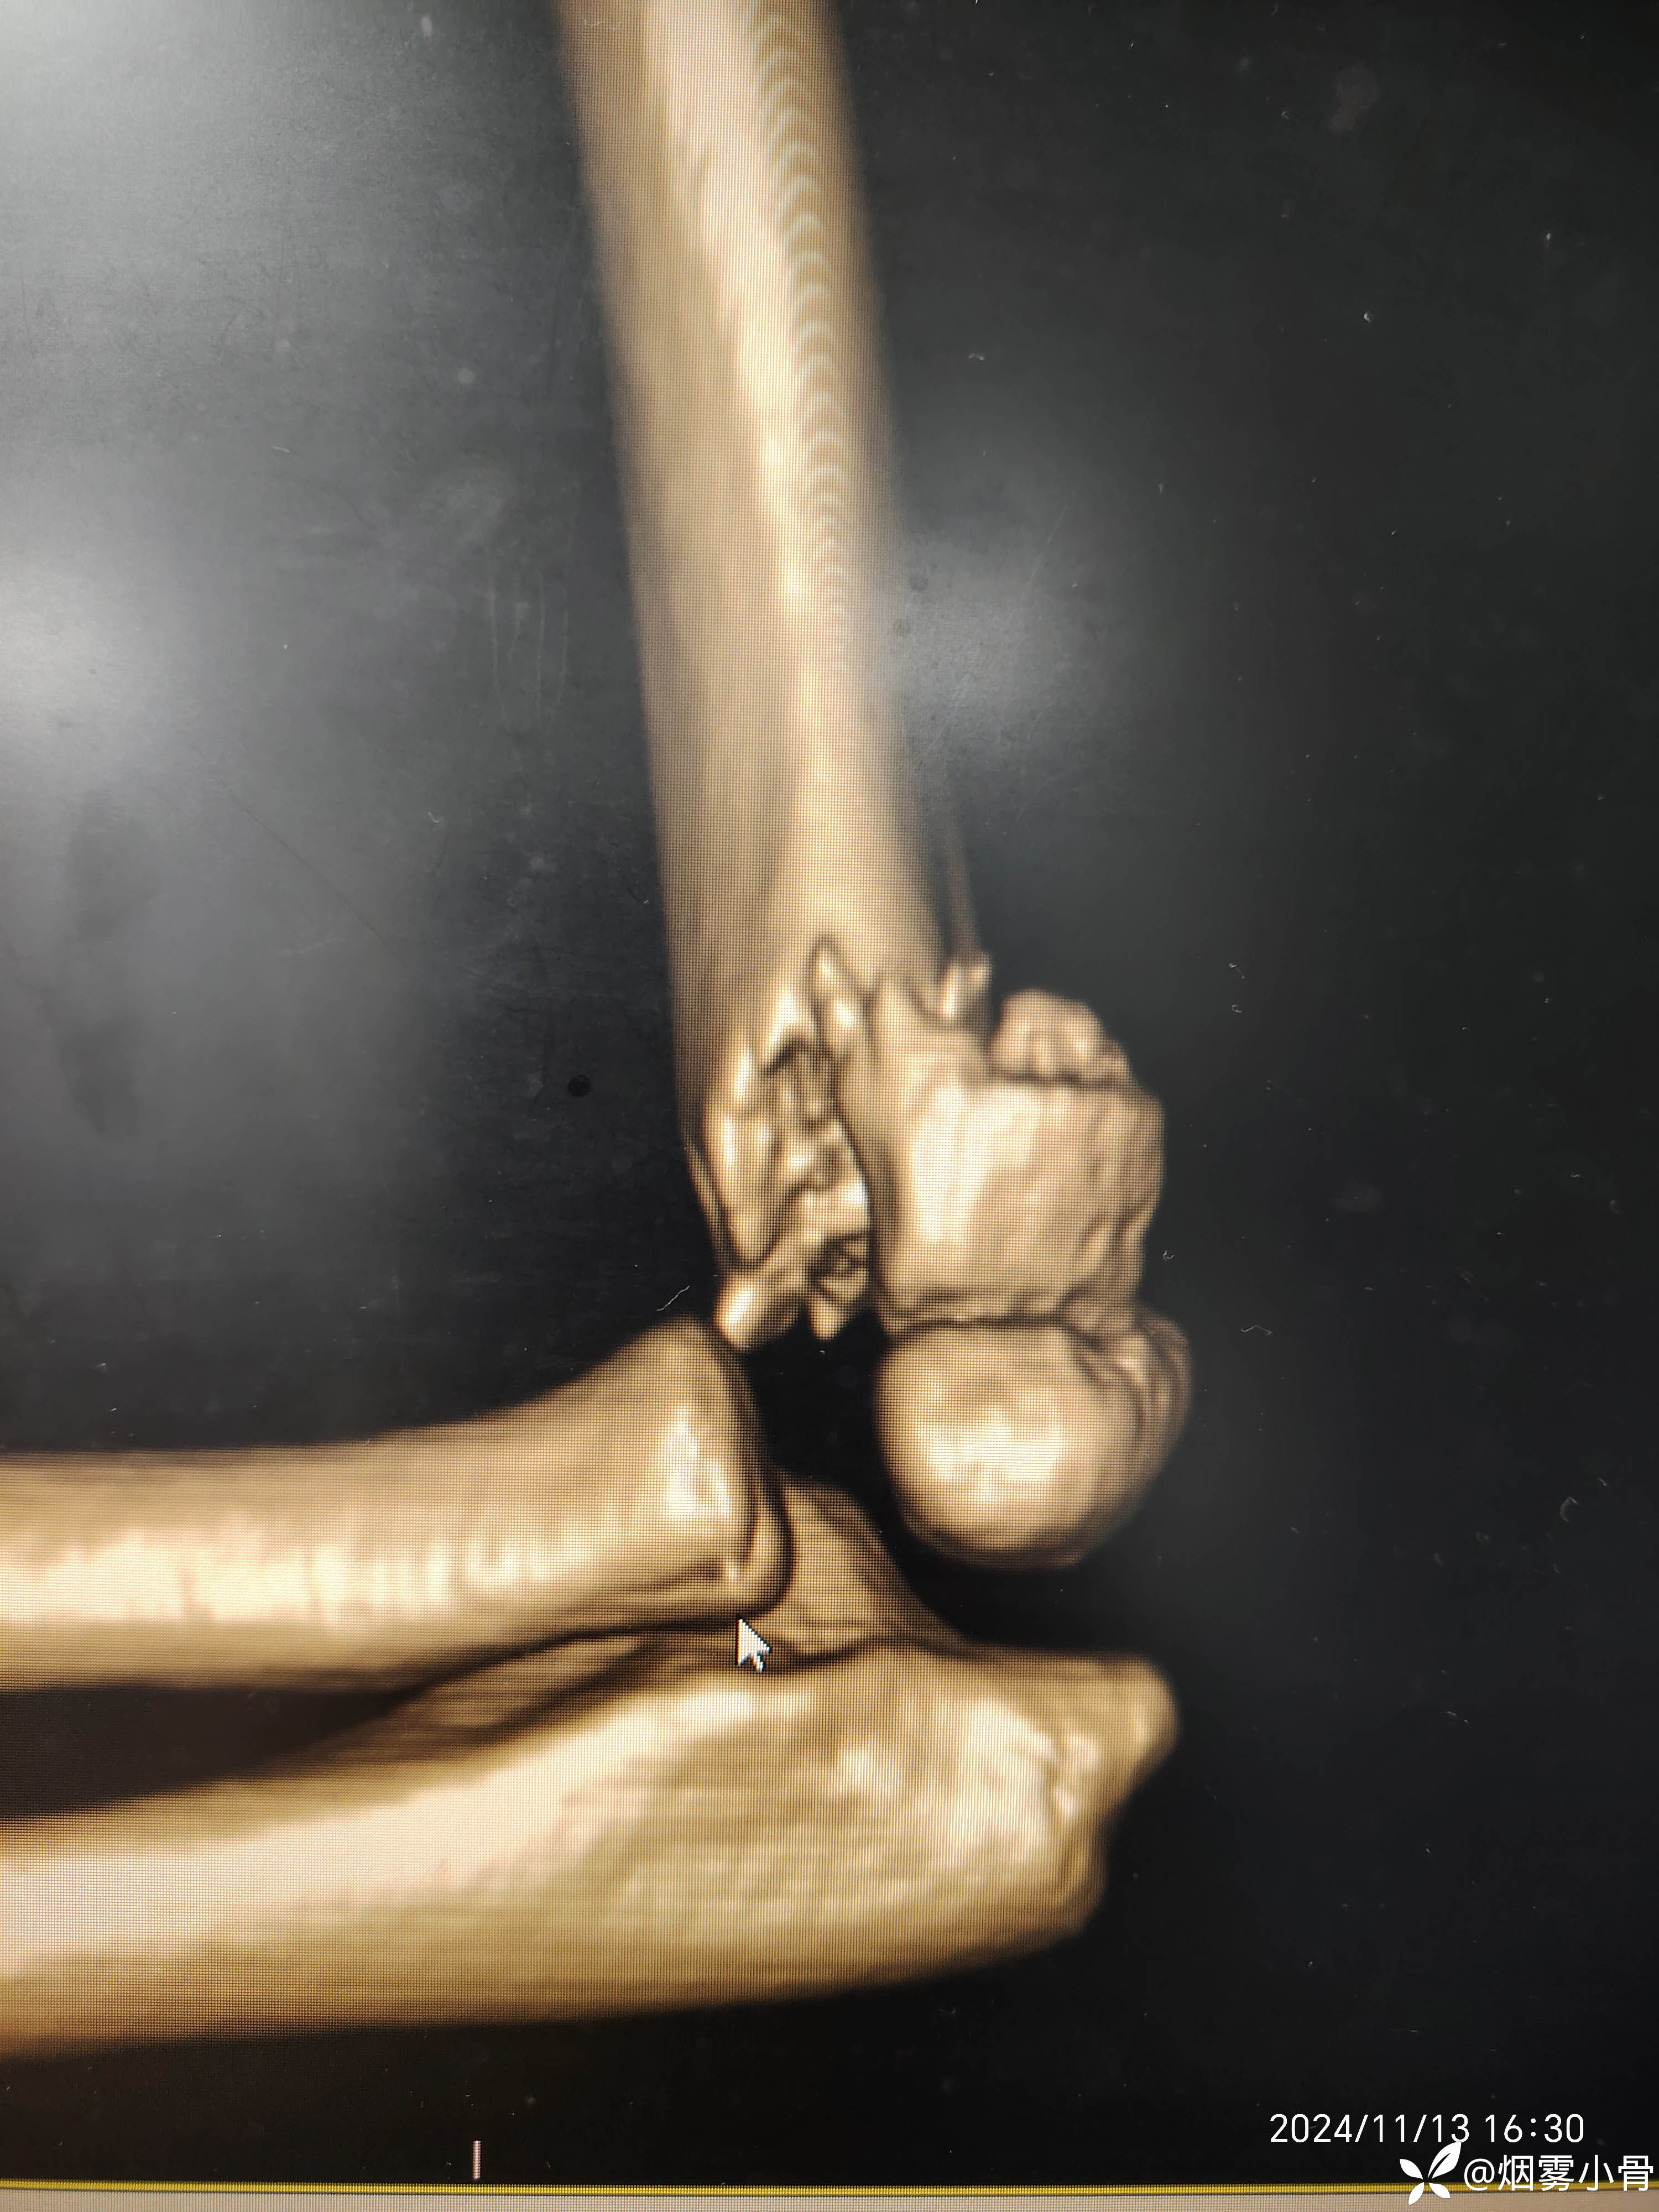

6岁肱骨髁上骨折,急诊30分钟完成零切开闭合复位克氏针内固定

【临床诊断】:左肱骨髁上骨折